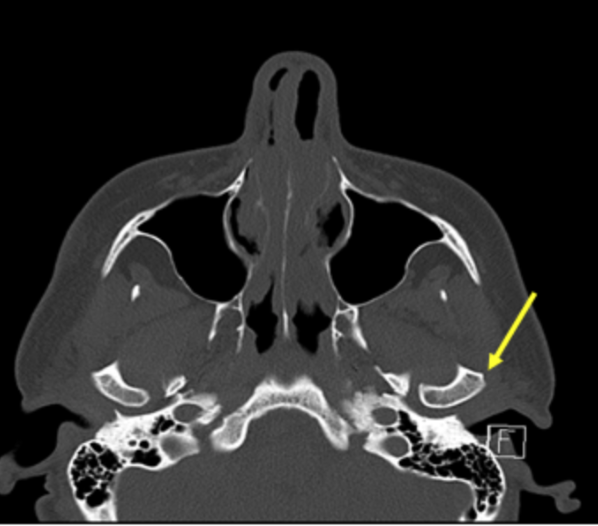

mandibular condyle

identify structure